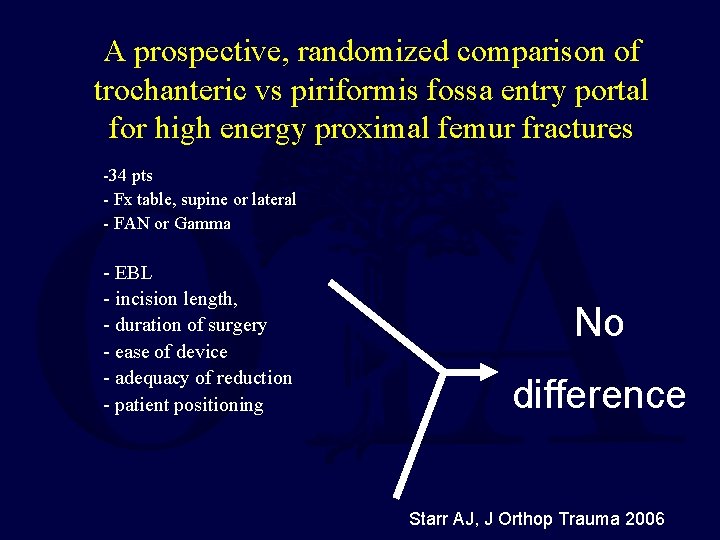

A prospective, randomized comparison of trochanteric vs piriformis fossa entry portal for high energy proximal femur fractures -34 pts - Fx table, supine or lateral - FAN or Gamma - EBL - incision length, - duration of surgery - ease of device - adequacy of reduction - patient positioning No difference Starr AJ, J Orthop Trauma 2006